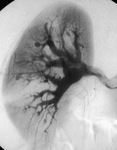

Angiografia mesentérica mostrando pequenos aneurismas e microaneurismas

Do acervo do Dr Loic Guillevin